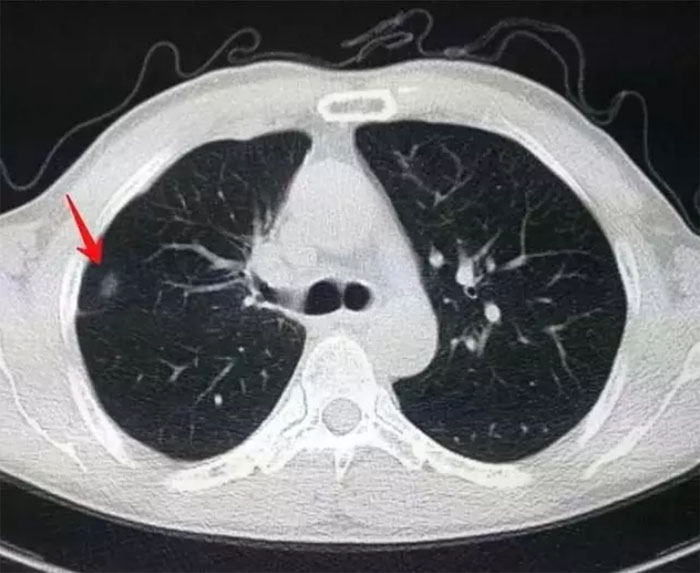

肺结节为小的局灶性、类圆形、影像学表现密度增高的阴影,可单发或多发,不伴肺不张、肺门肿大和胸腔积液。孤立性肺结节无典型症状,常为单个、边界清楚、密度增高、直径≤3 cm且周围被含气肺组织包绕的软组织影。

肺部小结节并不等于早期肺癌,肺内很多疾病都会形成结节,良性的如炎症、结核、霉菌、亚段肺不张、出血、等。因此肺内的小结节性病灶,可能的诊断可以说是多种多样,良性的包括炎性假瘤、错构瘤、结核球、真菌感染、硬化性肺细胞瘤等。恶性的则可能是原发性肺癌或肺内转移癌。当然部分良性病变,长时间之后也可能转化为恶性。据人群大样本的统计表明,直径大于25px的肺内单发小结节,恶性的占到一半以上。

这样的数据告诉我们,决不可轻视体检时无意发现的肺内小结节。CT检查发现的肺部小结节,必须要高度重视,因为其中有一定比例是早期肺癌,所以必要的早期检测筛查,是必不可少。